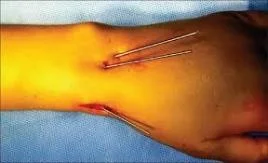

| Wires | • Simple, quick – Easy to apply – Easy to remove • Percutaneous • Not very stable – needs additional cast/splint • Mostly used in children | ![]() |